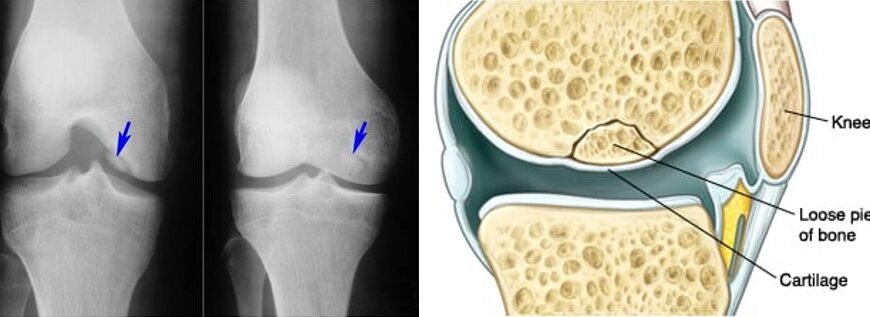

Хвороба Кеніга і інвалідність: як це впливає на життя? “Хвороба Кеніга — інвалідність”: ці слова можуть звучати страшно для тих, хто зіткнувся